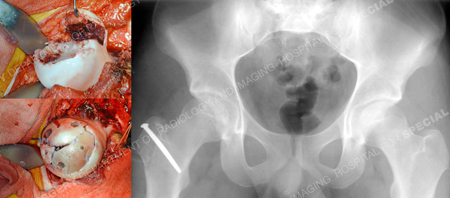

A Kocher-Langenbeck approach with a trochanteric flip and anterior dislocation of the hip was performed and the multiple fracture fragments were visualized. One was a free, thin osteochondral fragment found along the anterior surface of the femoral head. Considering the fact that the middle one-third of the femoral head was missing but involved the weight-bearing area, it was elected to obtain a frozen, femoral head osteochondral allograft. Once thawed, it was cut into place with an oscillating saw so as to fit into the defect. Autograft morselized bone was obtained from the greater trochanter and was placed underneath the allograft, the reconstructed medial femoral head fragment, and the osteochondral fragment. Two screws were placed into each loose fragment and aimed towards the intact femoral head. The screw heads were seated below the articular surface of the femoral head fragments. The femoral head was found to be congruous. The small, loose fragments from the periphery of the posterior wall were debrided as they were not felt to be requisite to the stability of the hip joint. The hip was located and congruity confirmed. He returned for regular follow-up visits and at 32 months and was working full time and returned to pre-injury activities. Radiographs of the hip showed a healed fracture of the femoral head and trochanteric osteotomy. There was a small amount of heterotopic ossification (Brooker stage I). There was no evidence of avascular necrosis (AVN). Crossing trabeculae were seen between the allograft and lateral femoral head with no evidence of collapse or ischemia in either.

Intraoperative photos of femoral head at time of exposure (top left image) and after fixation with screws (bottom left image) and postoperative anteroposterior x-ray of pelvis (right image).